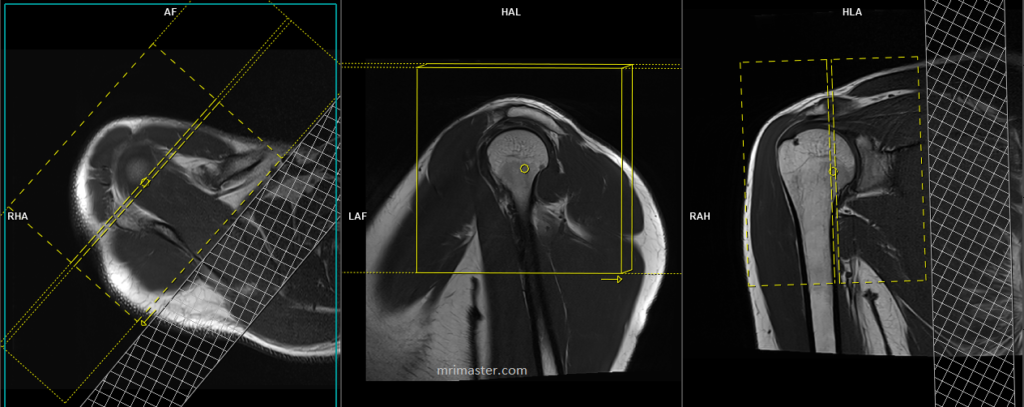

PD fat sat sagittal 3mm SFOV

Plan the sagittal slices on the axial plane and angle the positioning block perpendicular to the supraspinatus tendon. Verify the positioning block in the other two planes. Ensure an appropriate angle is set in the coronal plane, parallel to the humerus. Include enough slices to cover the entire shoulder joint, from the deltoid muscle to the scapular notch. Additionally, consider adding an oblique saturation band over the chest to minimize ghosting artifacts caused by breathing.

Parameters PD FS

TR 3000-4000 | TE 30-40 | SLICE 3 MM | FAT SAT SPAIR | PHASE A>P | MATRIX 320X320 | FOV 150-160 | GAP 10% | NEX(AVRAGE) 2 |